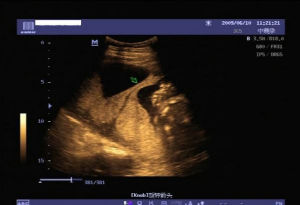

輪狀胎盤超聲診斷

1、輪狀胎盤的特徵性聲像圖改變為胎盤邊緣呈環狀或片狀突向羊膜腔,內部回聲與胎盤實質回聲相似,有出血或梗死者,內部可出現無回聲或低回聲區。

2、探頭對胎盤做放射狀掃查,即對胎盤邊緣做360度搜查觀察,有利於評估輪狀胎盤的程度。如後壁胎盤,由於胎體的影響,可能未能顯示而漏診。